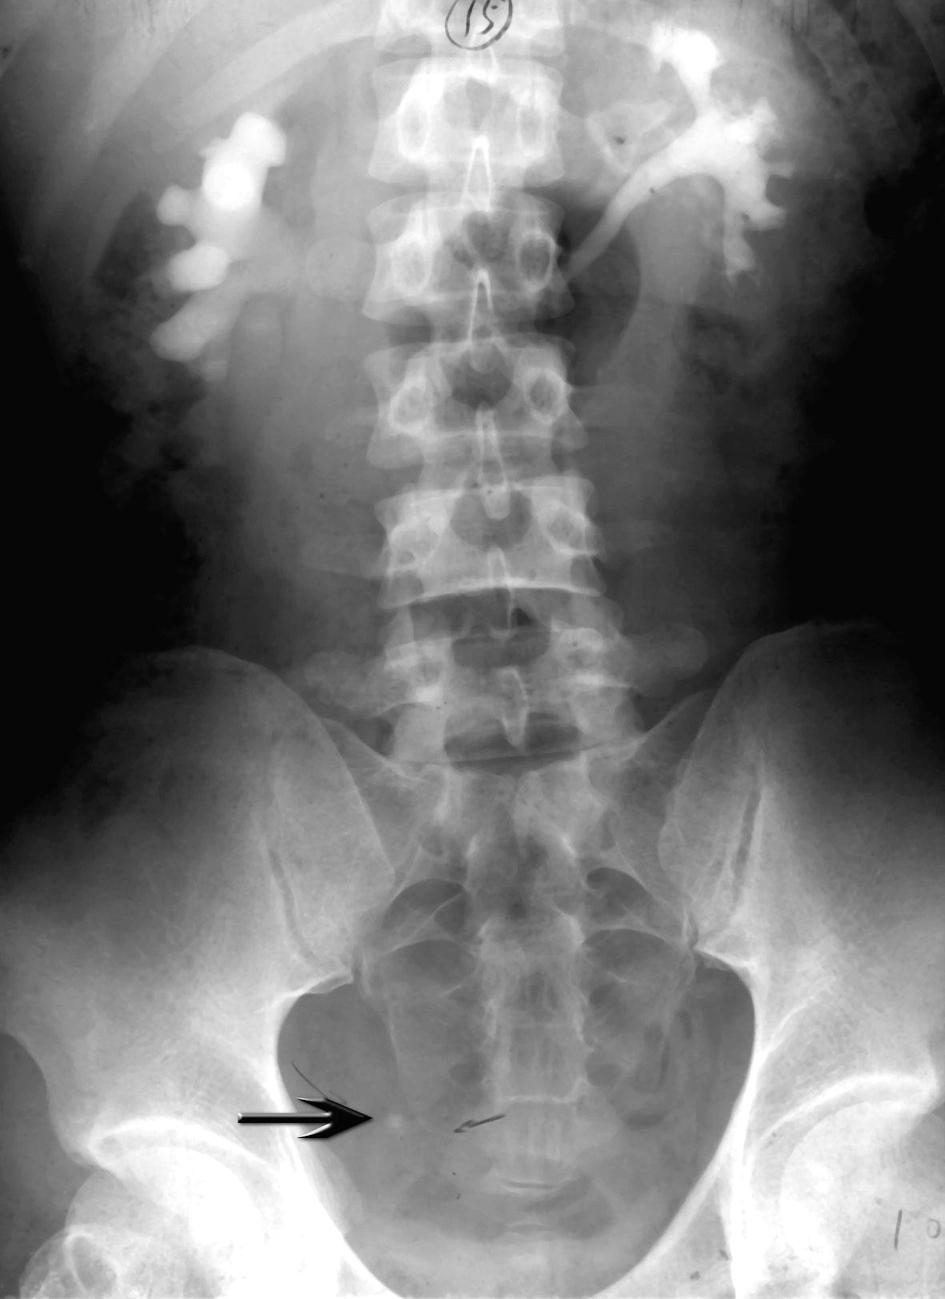

图 膀胱结石x光片

膀胱结石求诊

在拍摄脊柱部位的x光时,医生意外发现李先生膀胱和左肾竟然各有一个

【原创】膀胱结石(超大)不看会后悔哦.

膀胱结石